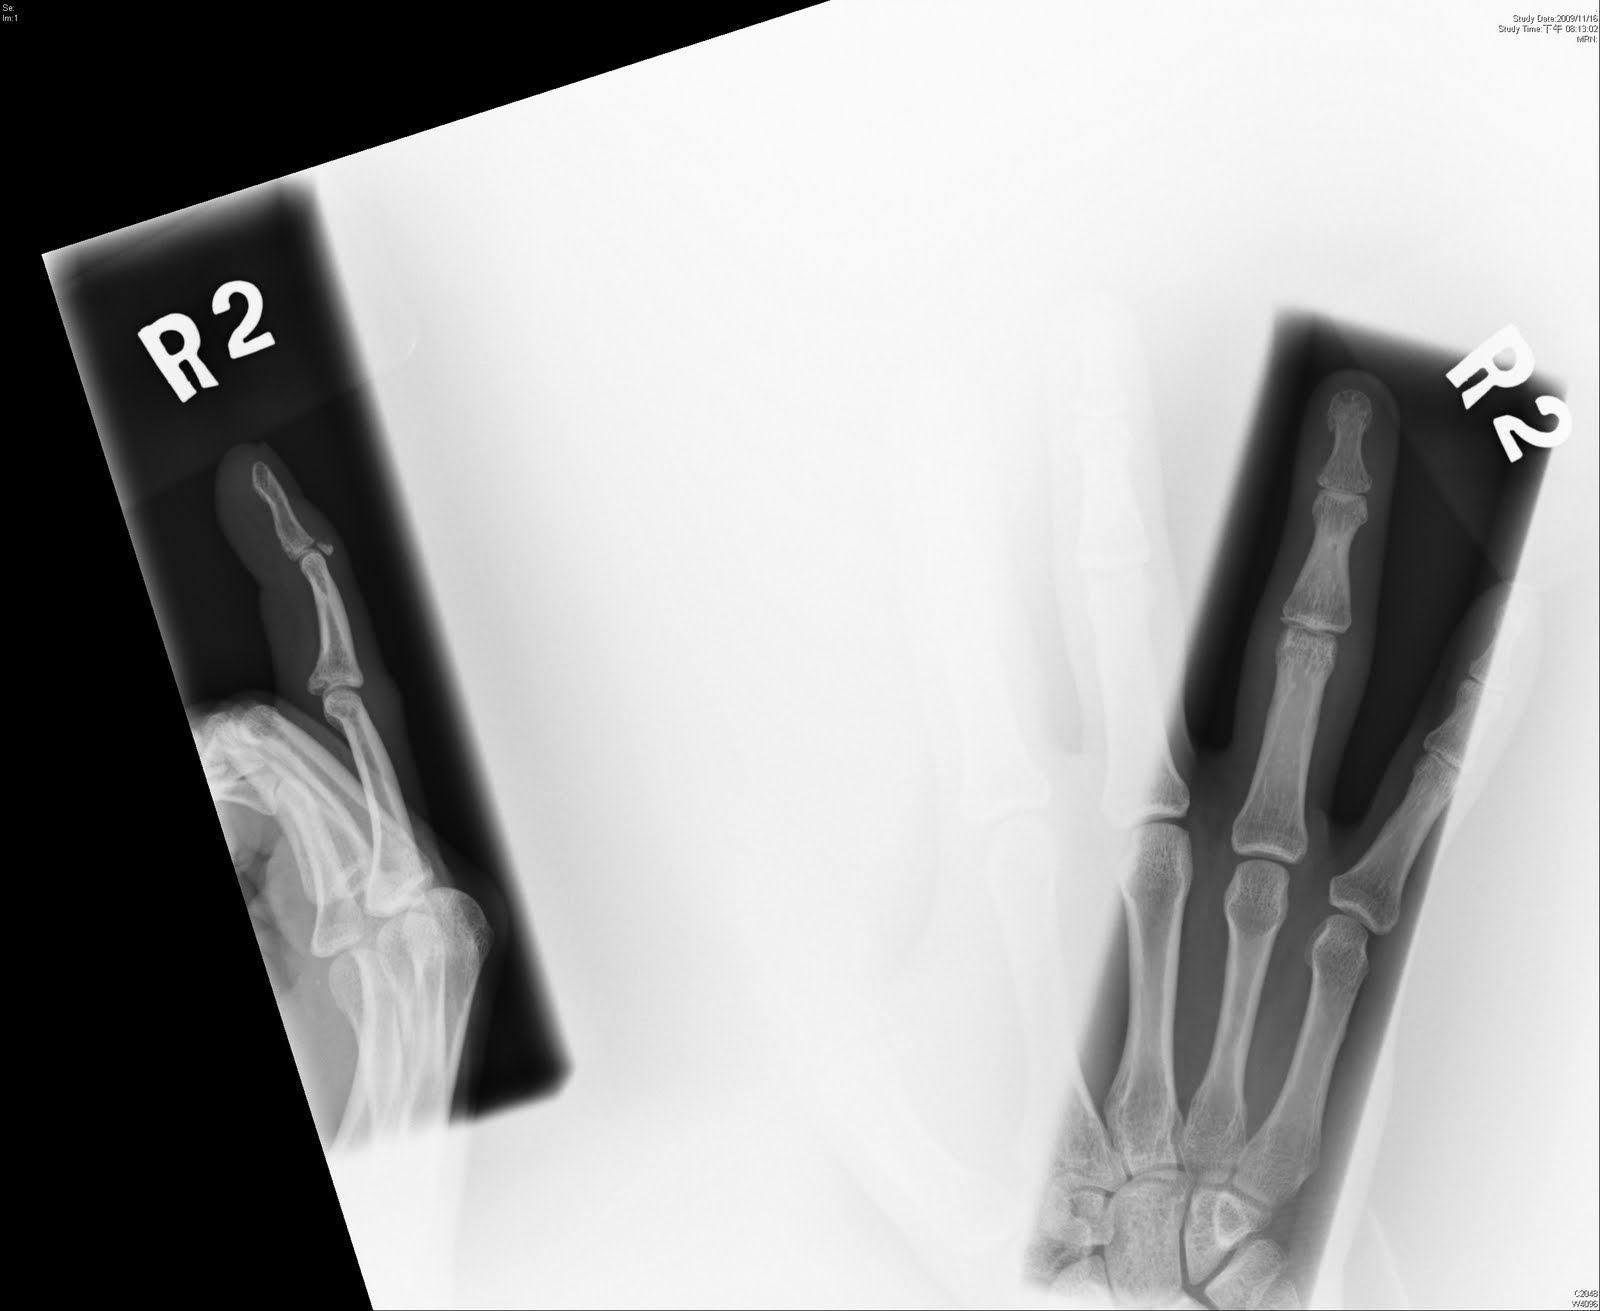

Avulsion fracture at base of middle phalanx | Radiology ...

Avulsion fracture at base of middle phalanx | Radiology ... from images.radiopaedia.org